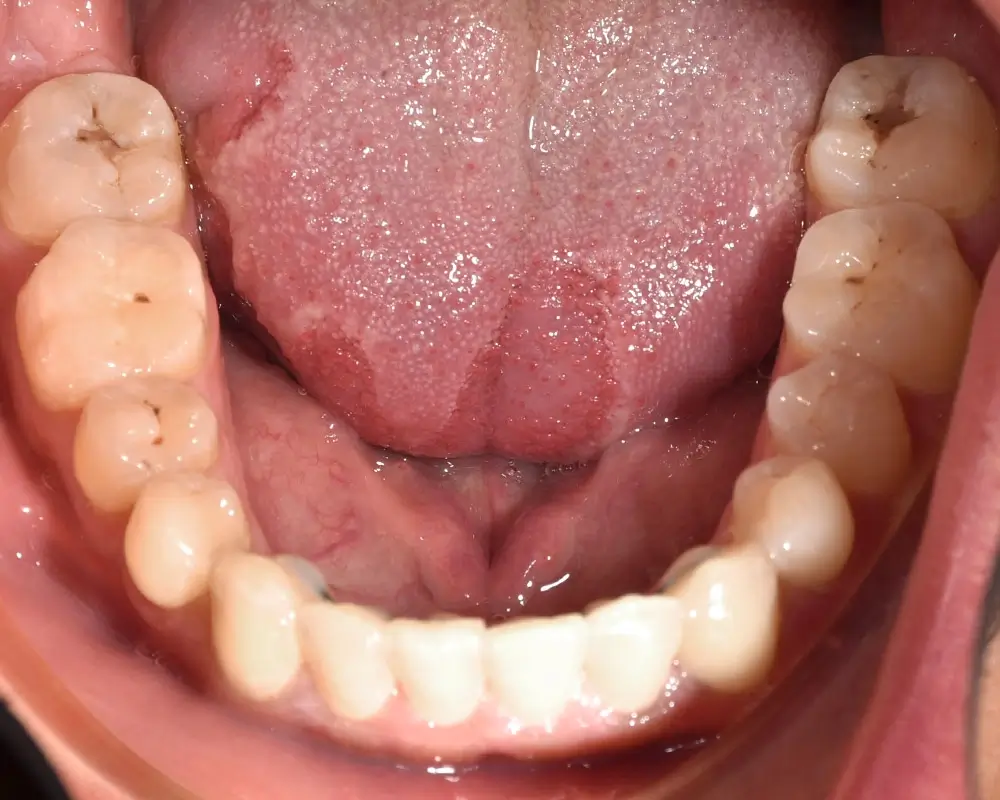

Открытый прикус - Кейс 3

Эффективность устранения дефекта прикуса посредством элайнеров FlexiLigner.

Результаты лечения